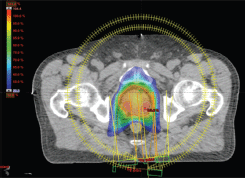

IMRT/IMAT techniques make it possible to deliver different levels of dose to different parts of the tumour (for instance, a hypoxic area of the tumour, identified by means of functional imaging, may receive a boost dose). Approaches using a simultaneous integrated boost (SIB) and the delivery of dose-escalated conventionally fractionated or hypo-fractionated RT using IMRT techniques are now being investigated as an alternative to conventional RT for different anatomical sites: breast [49, 50], head and neck [51, 52] prostate [53, 54]. Examples, using tomotherapy, of SIBs delivered to the breast tumour bed and to the dominant intra-prostatic lesions (DILs) are shown in Figures 1 and 2.

Figure 2. Axial view of a volumetric arc therapy (VMAT) treatment plan for prostate cancer delivered with RapidArc, with SIB to DILs.